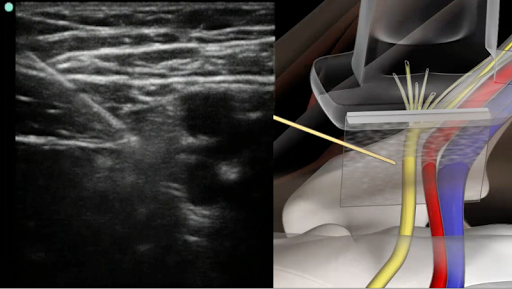

A unique system that combines live sonoanatomy via ultrasound scans, 3D animated anatomy and real time video of the performance of regional anaesthetic nerve blocks. All elements are combined and synchronised with audible narration.

* 3D Animated anatomical models, interlinked with live ultrasound scans.

* Annotated ultrasound screen shots.

A tab system gives the user access to anatomy, procedure, tips and equipment. The anatomy tab gives an overview of anatomy related to the specific block, it includes schematic diagram’s which can be expanded to full screen. The procedures tab is a full pictorial and text guide to the performance of the specific block, including annotated ultrasound screen captures to help visualise nerves. The tips tab contains useful advice related to the selected block, also included is advice on the use of ultrasound and local anaesthetics.